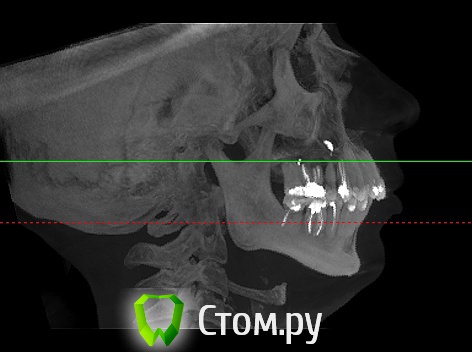

Гуля-Р Опубликовано 8 ноября, 2014 Автор Поделиться Опубликовано 8 ноября, 2014 И кривые зубы, и профиль, и прикус. Профиль думаю только хирургмческим путем. Ссылка на комментарий

Force Опубликовано 8 ноября, 2014 Поделиться Опубликовано 8 ноября, 2014 Это ответ на ваш вопрос. проблема не только в нижней, но и в верхней челюсти. Хороший ортодонт и хороший ортогнатический хирург помогут изменить ваше представление о себе Ссылка на комментарий